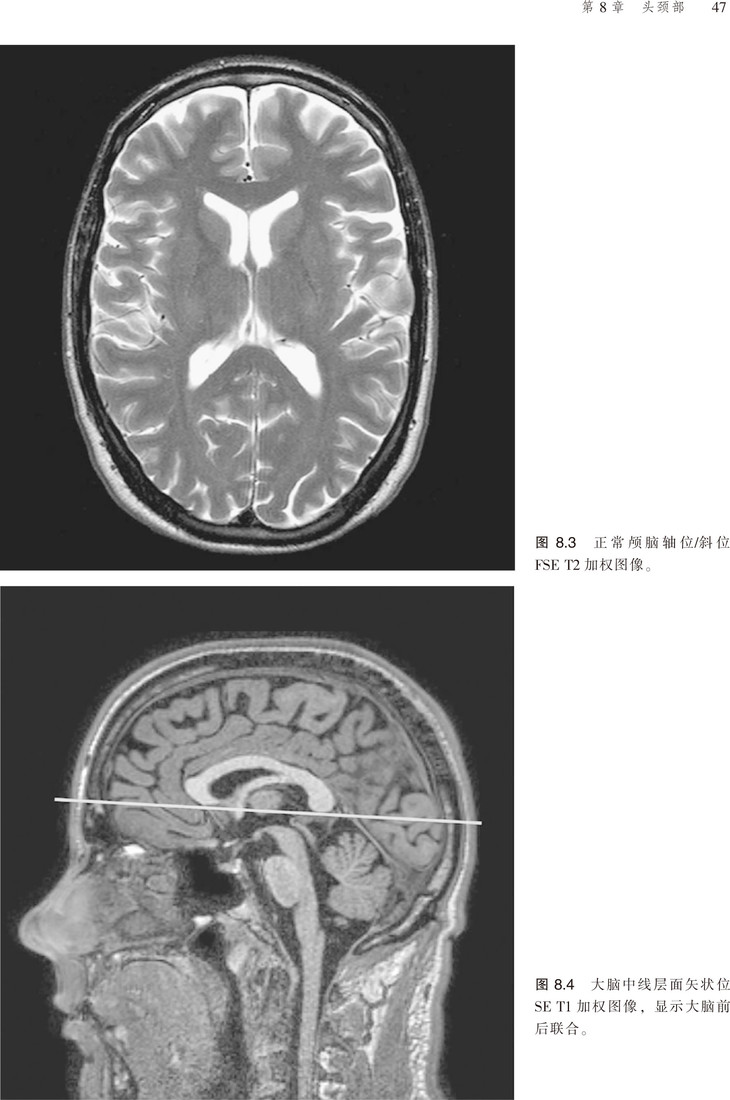

该书对脉冲序列、伪影、门控技术、预饱和技术等原理进行了讲解,且涵盖临床应用的相关参数,并就对比剂等以及受检者的安全性进行了分析。更为可贵的是该书不仅有应用解剖图谱,还有扫描的参照图,便于读者阅读,加深对书中内容的理解。